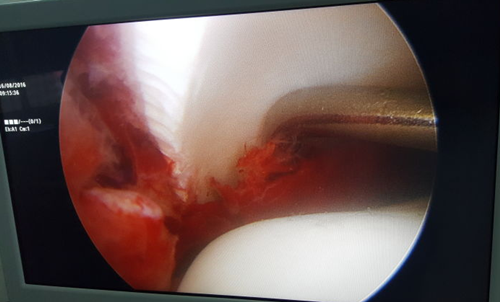

图为术中操作

境下用探钩清理骨折断端软组织及血凝块